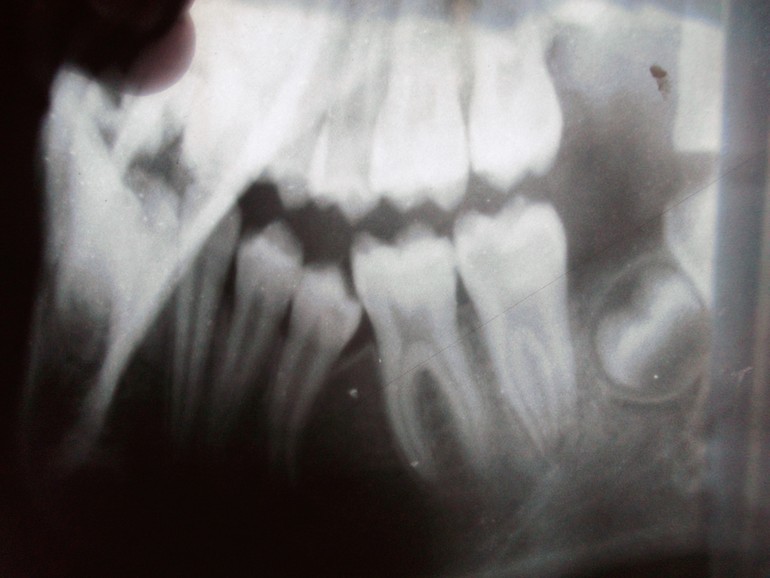

Я видела там пост. Кстати, периодические боли реально может давать семерка. По снимку видно глубокий кариозный процесс под пломбой. Внешне это не всегда заметно. Особенно если боли ночные... Такое характерно для пульпита. Проверьте семерку еще раз хорошенько. Может реально дело в ней, а не в пятерке. Вообще вам явно нужно показаться более компетентным врачам.

Так внешне и не видно. Кариес может развиться ПОД пломбой, если она поставлена плохо, не герметично. А это обычное дело для поликлиники. У старшей две пломбы, поставленные в детской госполиклинике пришлось переделывать. На снимке есть затемнение слева на семёрке. Если это кариес, то он запросто может давать такие боли. У меня так болела кариозная восьмерка. Тоже раз в месяц начинала ныть вся челюсть, спать не могла.

Болит где именно? В области пятерки? Или где зуб мудрости? Вообще по этому снимку сложно что-то понять, надо панорамный. Ну и ортодонт, да.

Это пятый зуб? Просто качество снимка совсем не очень... У вас раннего удаления там не было? Молочные зубы не удаляли?

внешне он почти вылез, а на снимке видно что сильно давит.

Снимок еще нечеткий, непонятно, что там между 5 и 6. Нет ли кисты?